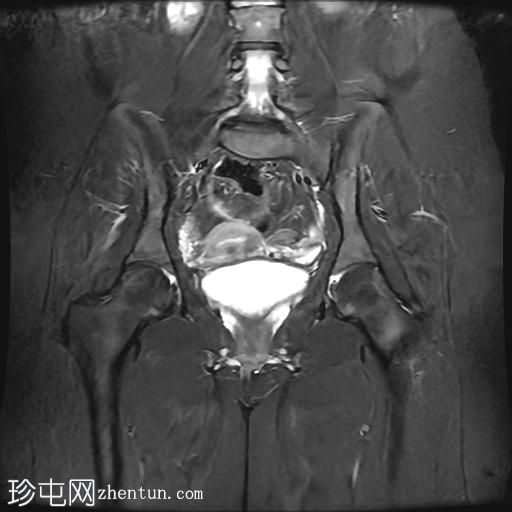

MRI

轴位

T2加权像

冠状位T2加权像

脂肪抑制像

臀中肌髂骨起点处前侧全层撕裂,伴有充满液体的间隙,以及髂骨髓水肿。

MRI结果符合臀中肌近端髂骨起点处全层撕裂的

影像

学表现。